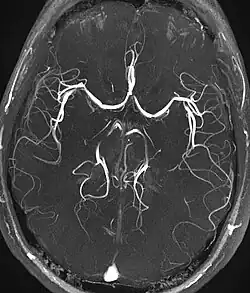

Magnetic resonance angiography

Time-of-flight MRA at the level of the Circle of Willis.

Magnetic resonance angiography (MRA) is a group of techniques based to image blood vessels. Magnetic resonance angiography is used to generate images of arteries (and less commonly veins) in order to evaluate them for stenosis (abnormal narrowing), occlusions, aneurysms (vessel wall dilatations, at risk of rupture) or other abnormalities. MRA is often used to evaluate the arteries of the neck and brain, the thoracic and abdominal aorta, the renal arteries, and the legs (the latter exam is often referred to as a "run-off").

Phase contrast

Phase contrast MRI (PC-MRI) is used to measure flow velocities in the body. It is used mainly to measure blood flow in the heart and throughout the body. PC-MRI may be considered a method of magnetic resonance velocimetry. Since modern PC-MRI typically is time-resolved, it also may be referred to as 4-D imaging (three spatial dimensions plus time).[51]